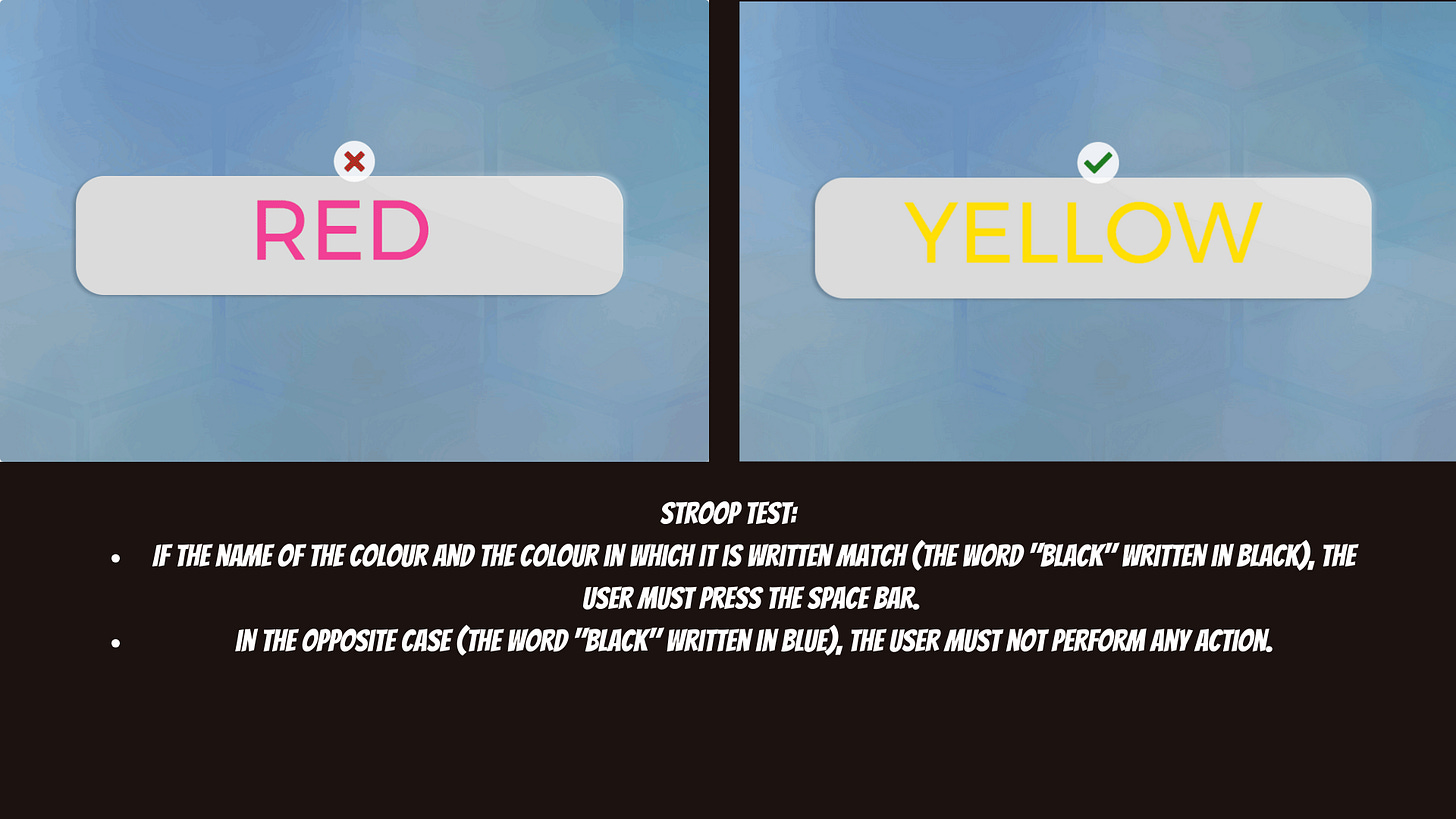

Imagine a bunch of 2-5 minute games that ask you to switch between different tasks, remember sequences of letters/numbers, spot the difference in images, etc. See below for some examples.

This experience took me back to my childhood memories. Especially for 3 or 4 (from about 20 tasks), I felt like I was completely wasting my time — wrong wrong wrong wrong wrong…..for about 3 minutes. But the frustration wasn’t about being wrong; it was about the fact that a millisecond after each wrong answer, I knew that I had made a mistake that I never intended to make. It’s the feeling of, “d*mn, no, no I didn’t mean that, can we go back,” 80 times in a row. For example, I successfully clicked on every ‘3’ when I was supposed to click on every other number but 3. Or, I stared at a screen for 3 minutes to see which direction a pool of fish was moving towards, when I was full-heartedly certain that the fish were actually not moving anywhere. I swore and laughed at myself multiple times. A very humbling experience, especially because I had assumed I would have an easy time because my ADHD symptoms have been mostly long gone. By the end of the night, I felt that I could comfortably re-diagnose myself.